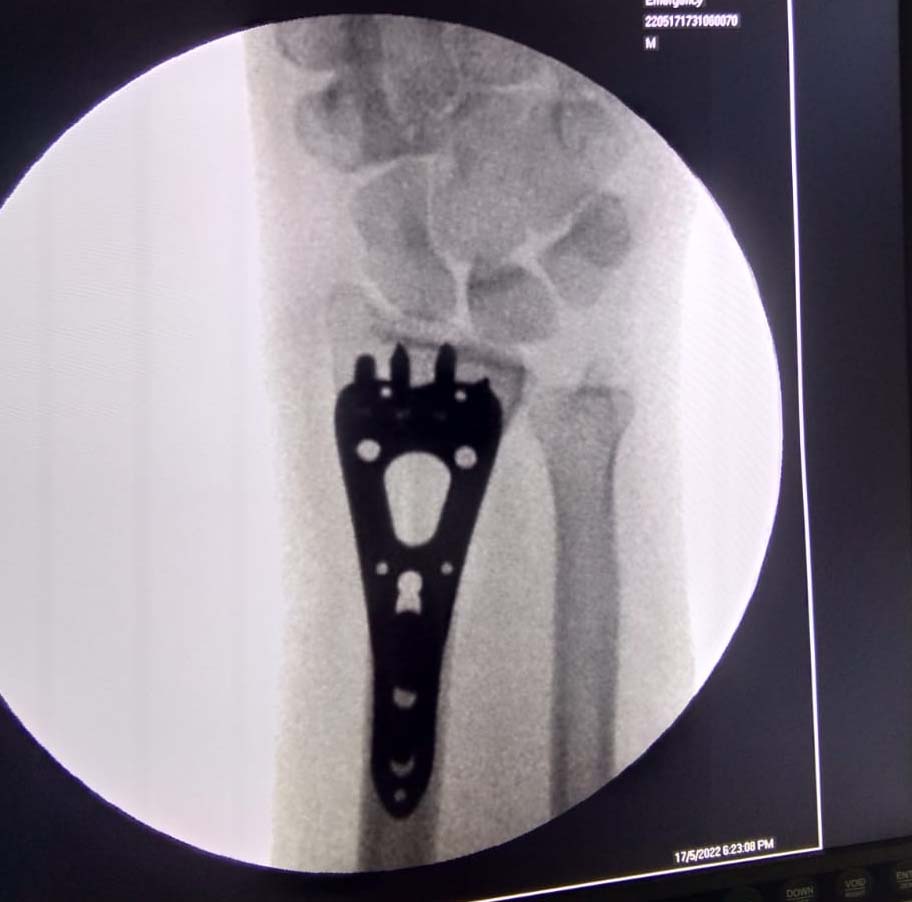

Trauma Fracture